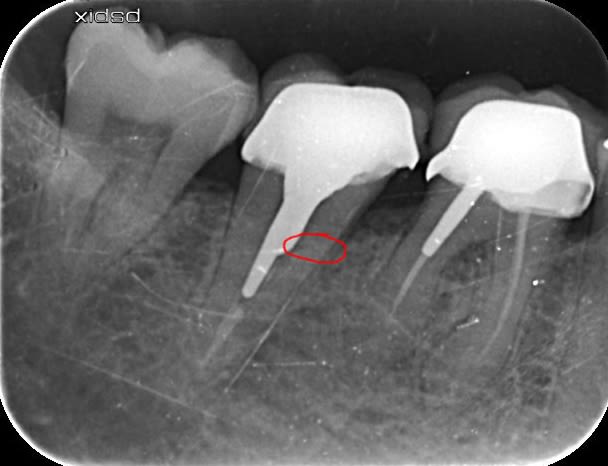

Bonjour j'ai posé cette couronne et fait le traitement endo de 47 il y a 2 mois

depuis le patient a mal a la percussion...

Anatomie atypique, j'avais 2 canaux se rejoignant à l'apex.

Je ne comprends pas d'ou peut provenir cette douleur...

Si vous avec une idée, je suis preneur...

merci!